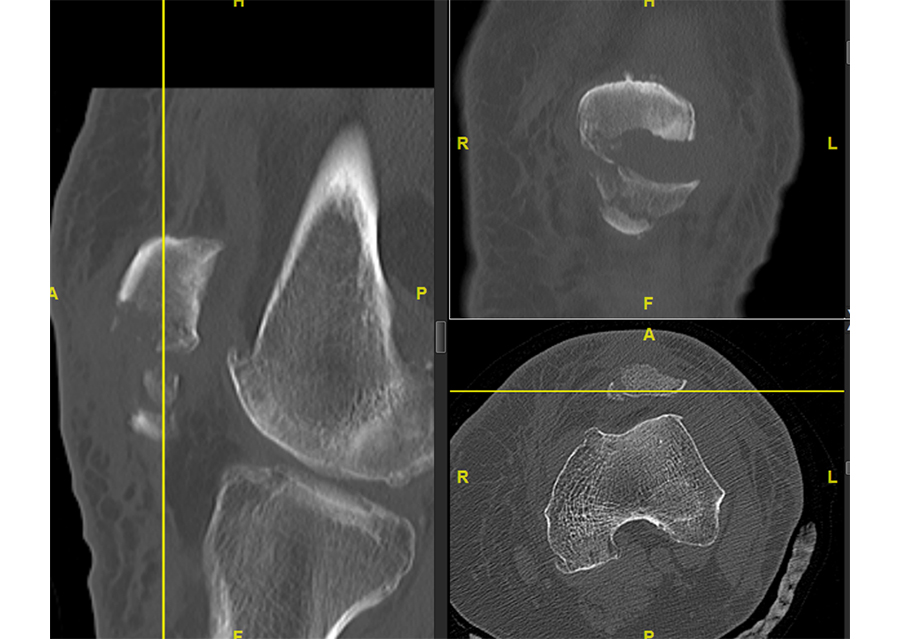

A CT scan was performed to assess the complexity of the fracture pattern (Fig 6).